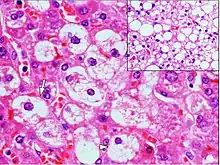

| Micrograph demonstrating marked (macrovesicular) steatosis in non-alcoholic fatty liver disease. Masson's trichrome stain. | |

Steatosis reflects an impairment of the normal processes of synthesis and elimination of triglyceride fat. Excess lipid accumulates in vesicles that displace the cytoplasm. When the vesicles are large enough to distort the nucleus, the condition is known as macrovesicular steatosis; otherwise, the condition is known as microvesicular steatosis. While not particularly detrimental to the cell in mild cases, large accumulations can disrupt cell constituents, and in severe cases the cell may even burst.

Histology

Histologically, steatosis is physically apparent as lipid within membrane bound liposomes of parenchymal cells.[2] When this tissue is fixed and stained to be better viewed under a microscope, the lipid is usually dissolved by the solvents used to prepare the sample. As such, samples prepared this way will appear to have empty holes (or vacuoles) within the cells where the lipid has been cleared. Special lipid stains, such as Sudan stains and osmium tetroxide are able to retain and show up lipid droplets, hence more conclusively indicating the presence of lipids. Other intracellular accumulations, such as water or glycogen, can also appear as clear vacuoles, therefore it becomes necessary to use stains to better determine what substance is accumulating.

Histological section of a mouse's liver showing severe steatosis. The clear vacuoles contained lipid in life; however, histological fixation caused it to be dissolved and hence only empty/clear spaces are seen.

Micrograph of fatty liver showing lipid steatosis. H&E stain.

Steatosis with a centrilobular pattern, which is the general tendency for steatosis in adults.[11]